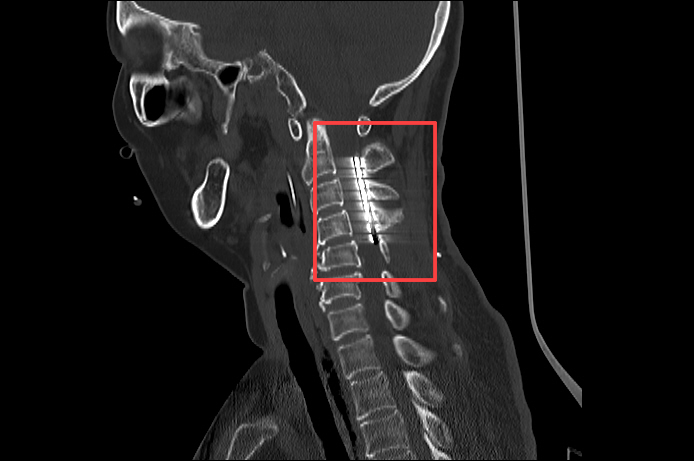

术中,电极被精准植入颈髓C2-C4水平硬膜外,通过脉冲刺激激活上行网状系统,促进脑皮层代谢与电活动。

▲神经外科团队为张女士行临时脊髓电刺激术(ST-SCS)

▲术后CT:电极植入位置精准

王文华主任表示:“SCS并非简单‘通电’,而是通过科学调控唤醒沉睡的神经网络。”SCS是一项成熟的手术,目前已较为明确SCS(脊髓电刺激)对昏迷促醒是有效的。SCS(脊髓电刺激)是通过在颈髓C2-C4水平硬膜外放置刺激电极,脉冲刺激经上行网状激活系统传至大脑皮层,增加脑局部葡萄糖代谢率及脑血流,促进兴奋性递质释放,增强意识冲动及脑电活动,最终达到促醒的目的。“这项技术为脑损伤患者提供了‘二次生命’的可能,更是对生命尊严的深刻诠释。”王文华主任还指出:“SCS(脊髓电刺激)近年来在神经学和康复医学领域备受关注。目前SCS的适应征较多,包括:1、促醒;2、缓解疼痛(带状疱疹等);3、改善肌肉痉挛(脑出血或脑外伤后);4、防止肌肉萎缩;5、增强肌力(脑出血或脑外伤后偏瘫);6、改善二便控制;7、糖尿病足等。”